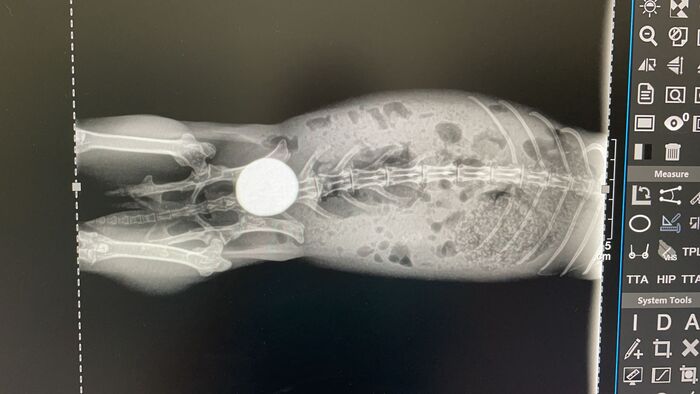

Piedras riñones / vejiga

Este es el caso de un conejito que sufría de colapso en la vejiga, como podréis ver en las radiografías tiene una cálculo enorme que le ocupa la vejiga entera, esto le producía un gran dolor y la imposibilidad de orinar, por lo que los riñones sufrían riesgo de colapso en cualquier momento. Tenía graves problemas digestivos también causados por dolor y por una parálisis en el intestino (íleo paralítico), algo que es muy grave en conejos, no podía digerir bien la comida y dejó de comer, antes de ello tuvo diarrea un tiempo.